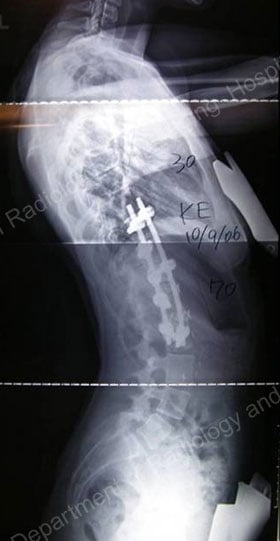

Figures 11 & 12: Postsurgical posterior (lower left) and lateral (lower right) X-rays – results achieved with an anterior approach.